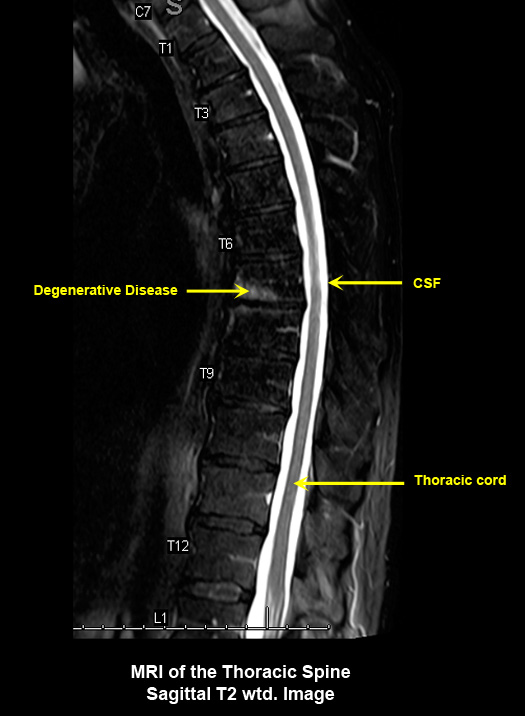

MR Brain and Spine